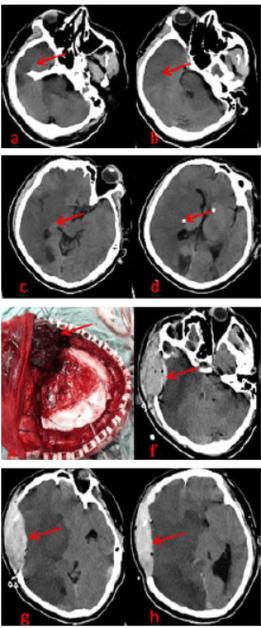

- 影像学检查:头颅CT平扫是首选的快速检查,可以快速排除脑出血,并初步判断梗塞的范围和是否有早期脑水肿迹象,如果条件允许,会尽快进行头颅MRI+DWI,能更早、更准确地发现梗塞灶。

- 血管内治疗(机械取栓):如果患者是大血管闭塞(如大脑中动脉),且在发病后6-24小时内(根据影像评估符合条件),医生会建议进行介入手术,通过导管将取栓支架送到堵塞的血管处,直接将血栓取出,恢复血流,这是治疗大血管闭塞最有效的方法,能显著改善预后。